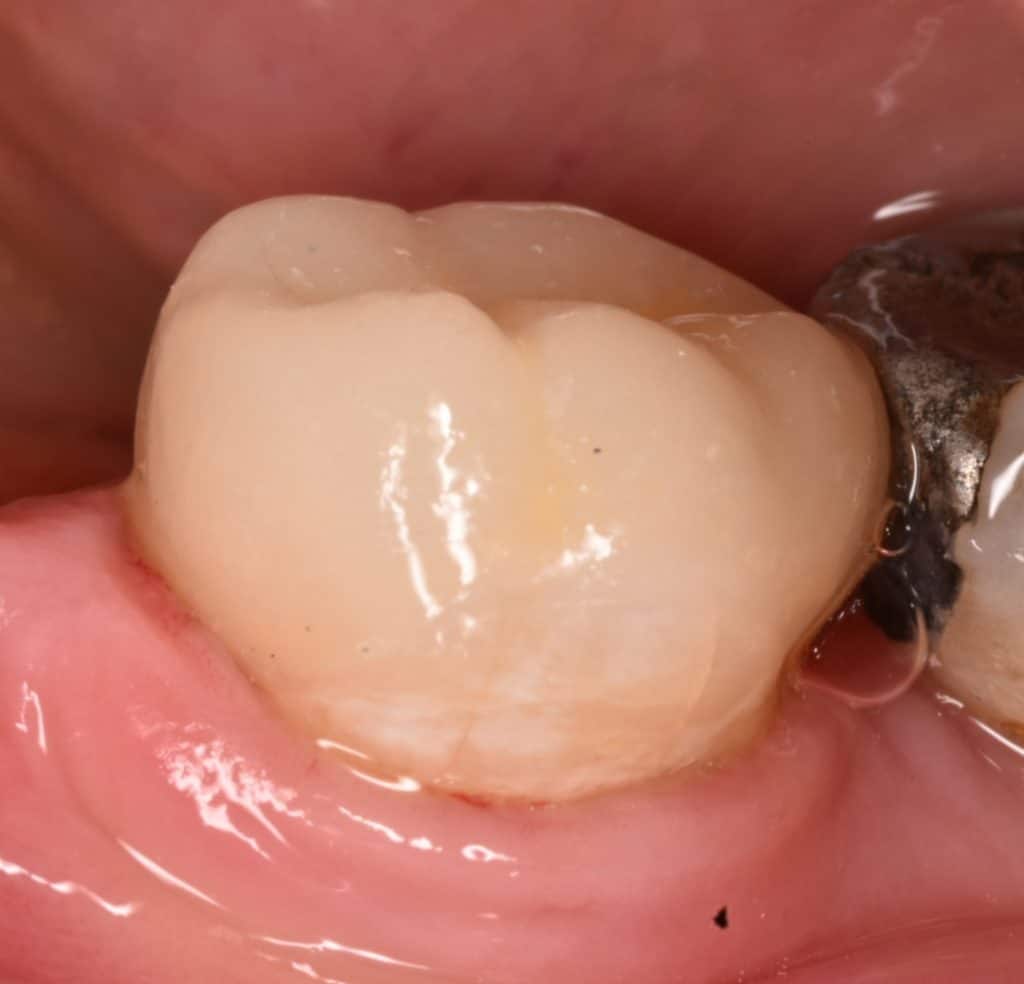

Another view for the preparation

Impression taking and temporization